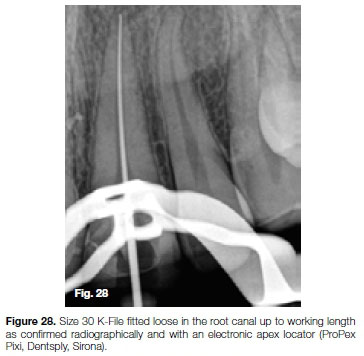

Having removed the fractured instrument, a size 30 K-File was fitted loose in the root canal up to working length as confirmed radiographically and with an electronic apex locator (ProPex, Dentsply, Sirona). According to the file selection criteria outlined by Van der Vyver et al. (2019)38 for WaveOne Gold files, a size large WaveOne Gold File (45/05) was selected for canal preparation.